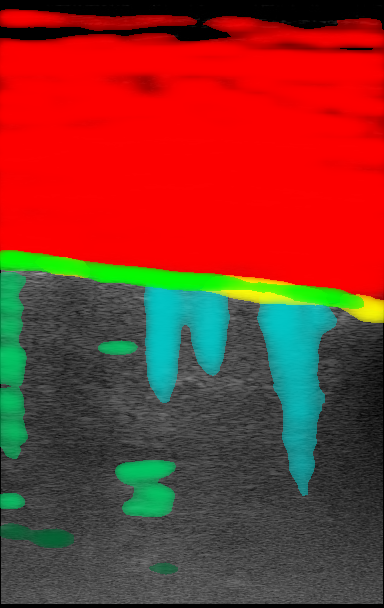

Figure 1 is an example segmentation label, thresholded by confidence to show the distribution of confidences in a single example. As the confidence threshold increases, the resulting segmentation labels get more refined. However, there may be a loss of features in the labels once the thresholds get sufficiently higher than the expert’s confidence in that feature’s appearance. For example, vertical lines disappear once the threshold becomes 40% in Figure 1. By thresholding the confidence labels this way and conducting further analysis with downstream tasks, we can gain a sense of how prominent these LUS features need to be for them to be clinically relevant.

| LUS Image | Soft Label | |||||||

|---|---|---|---|---|---|---|---|---|